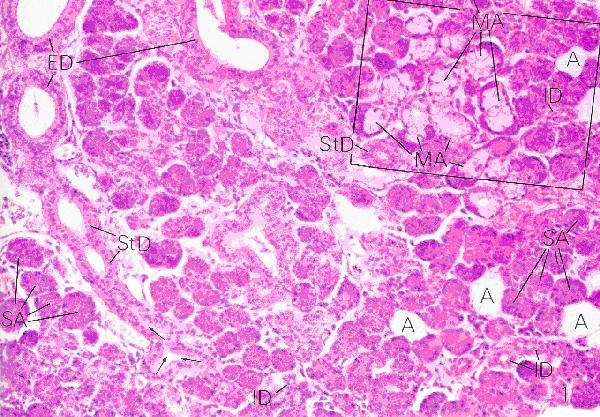

Plate 67 (Fig. 2)

Ross and Romrell p. 413

Mucinous Secretory Units

- The units appear larger and paler and in cross-section the cells of the units appear more tubular than round

- The nuclei are flattened and located against the bases of the cells

- The cytoplasm is pale staining due to the mucus that washes out during the preparation of the specimen

- The lumens of the units are large and prominent

Mixed Secretory Units

- These units consists of serous and mucinous alveoli or a combination thereof mucinous-serous alveolus

- The latter consists of a mucinous alveolus with a serous demilune which secretes into the lumen of the mucinous alveolus via intercellular ductules

Plate 68 (Fig. 2)

Ross and Romrell p. 415